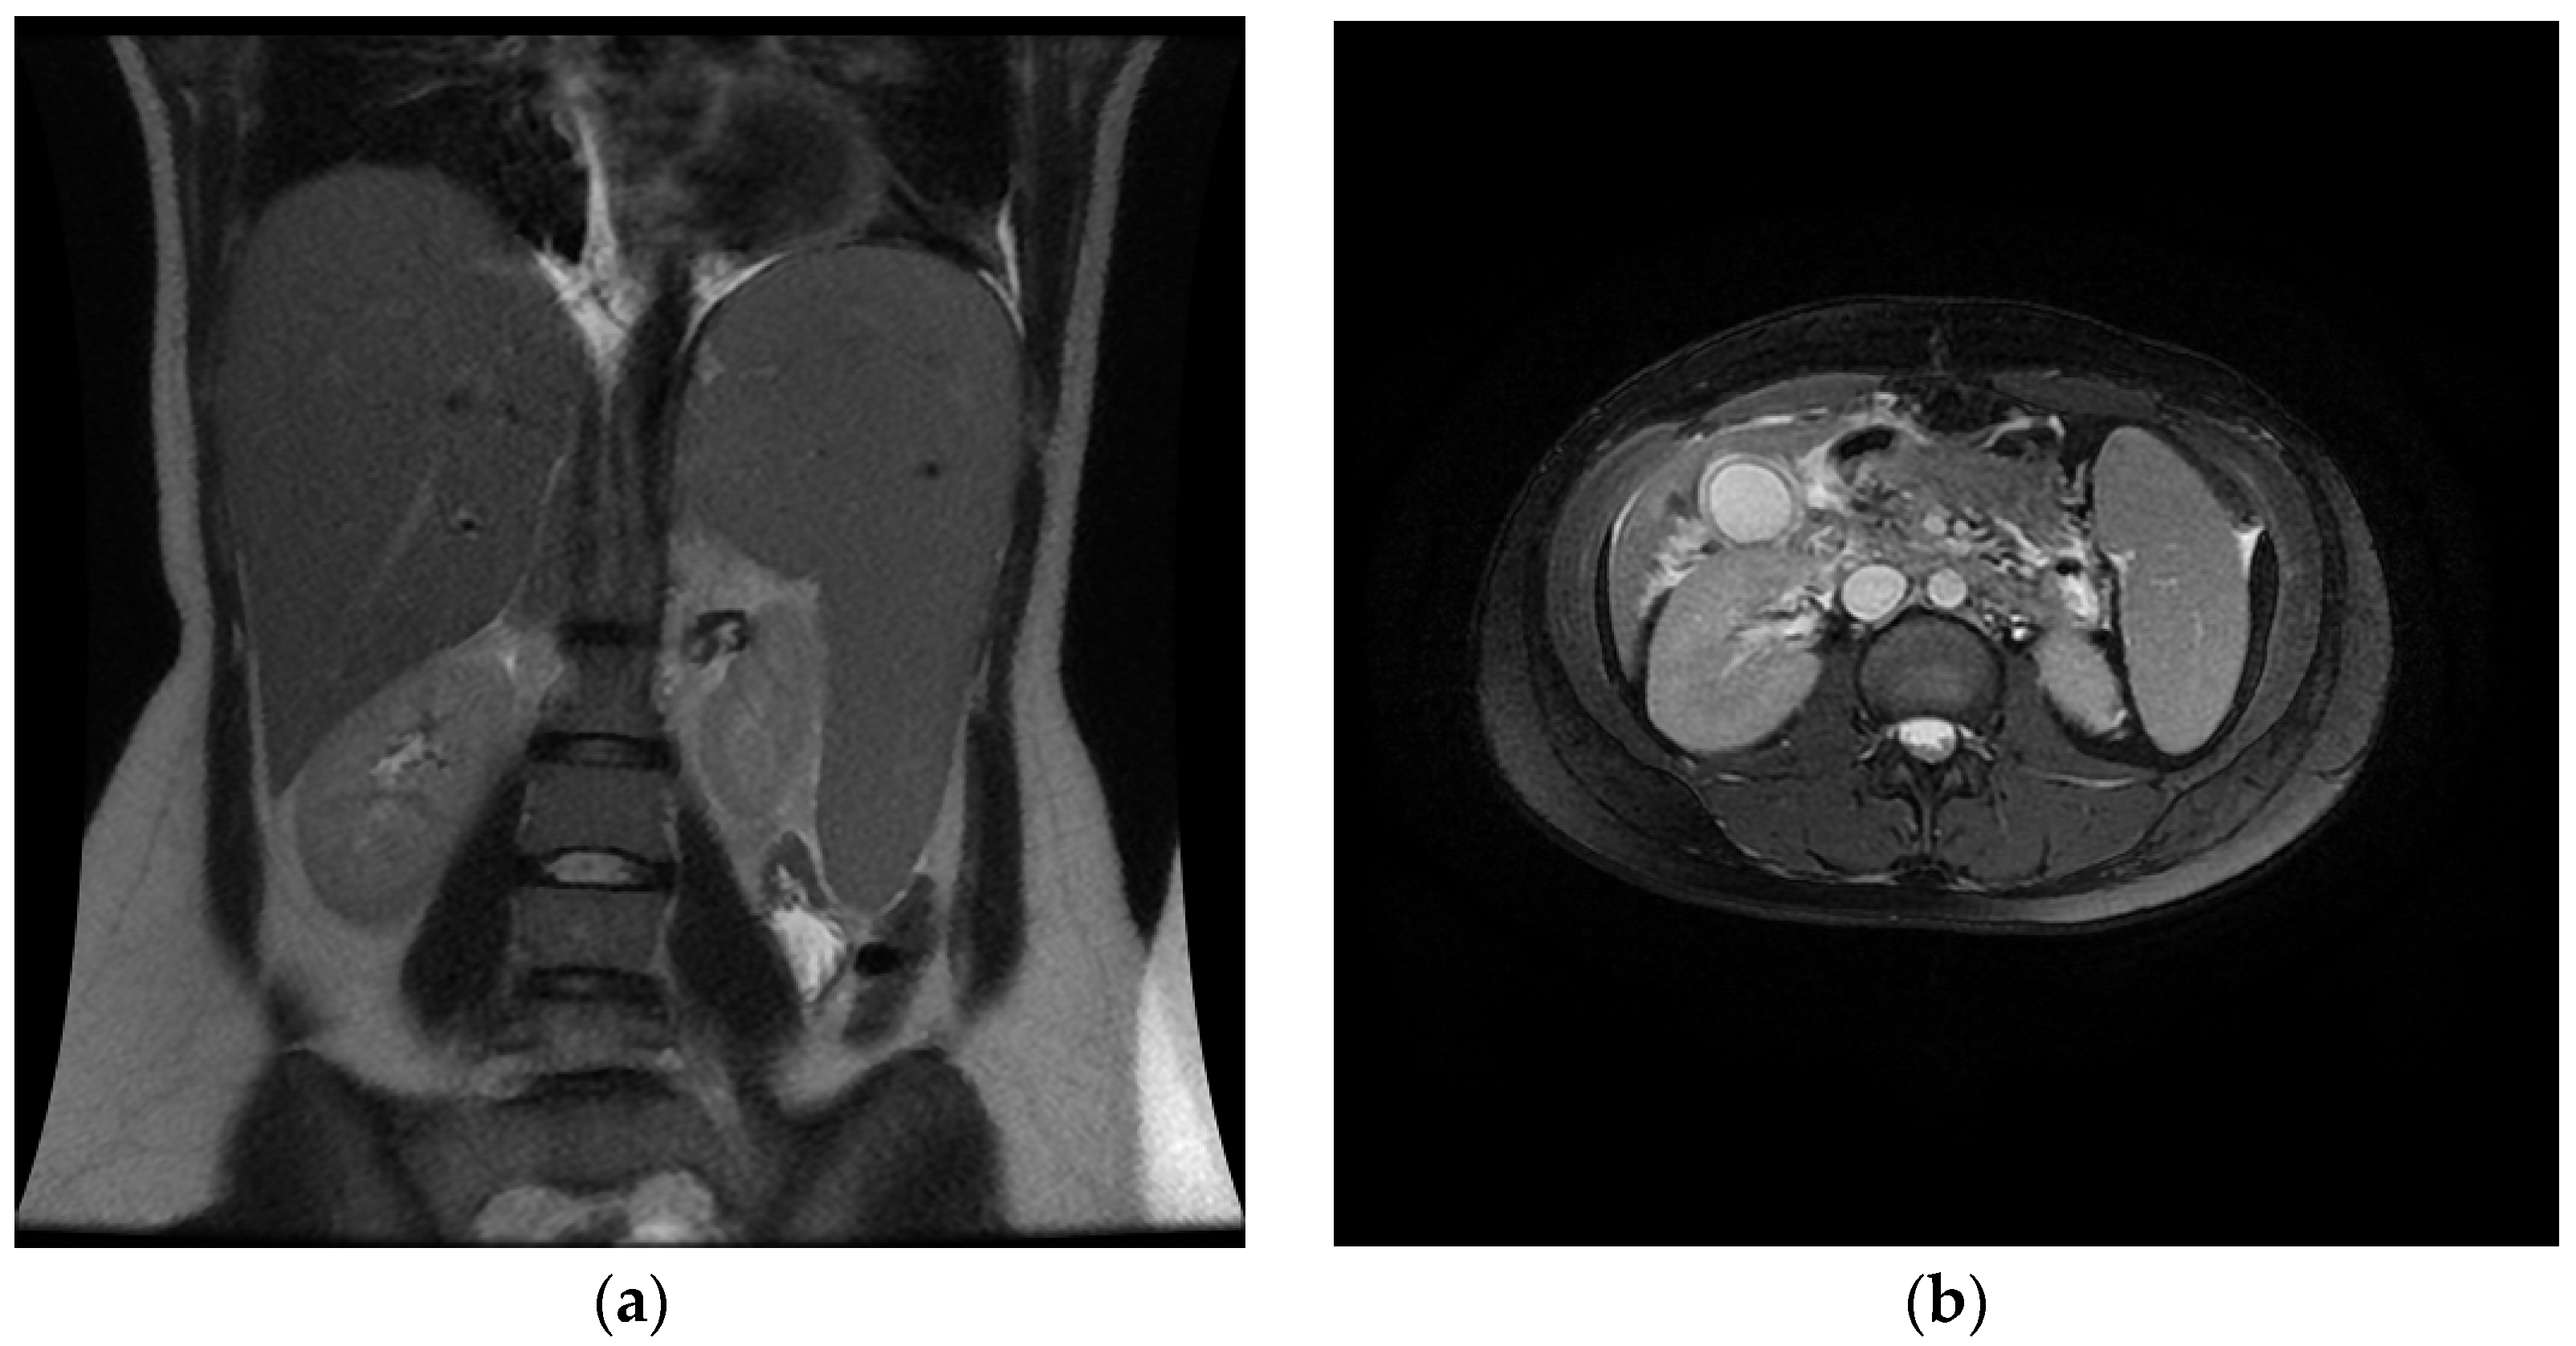

3. Case Report